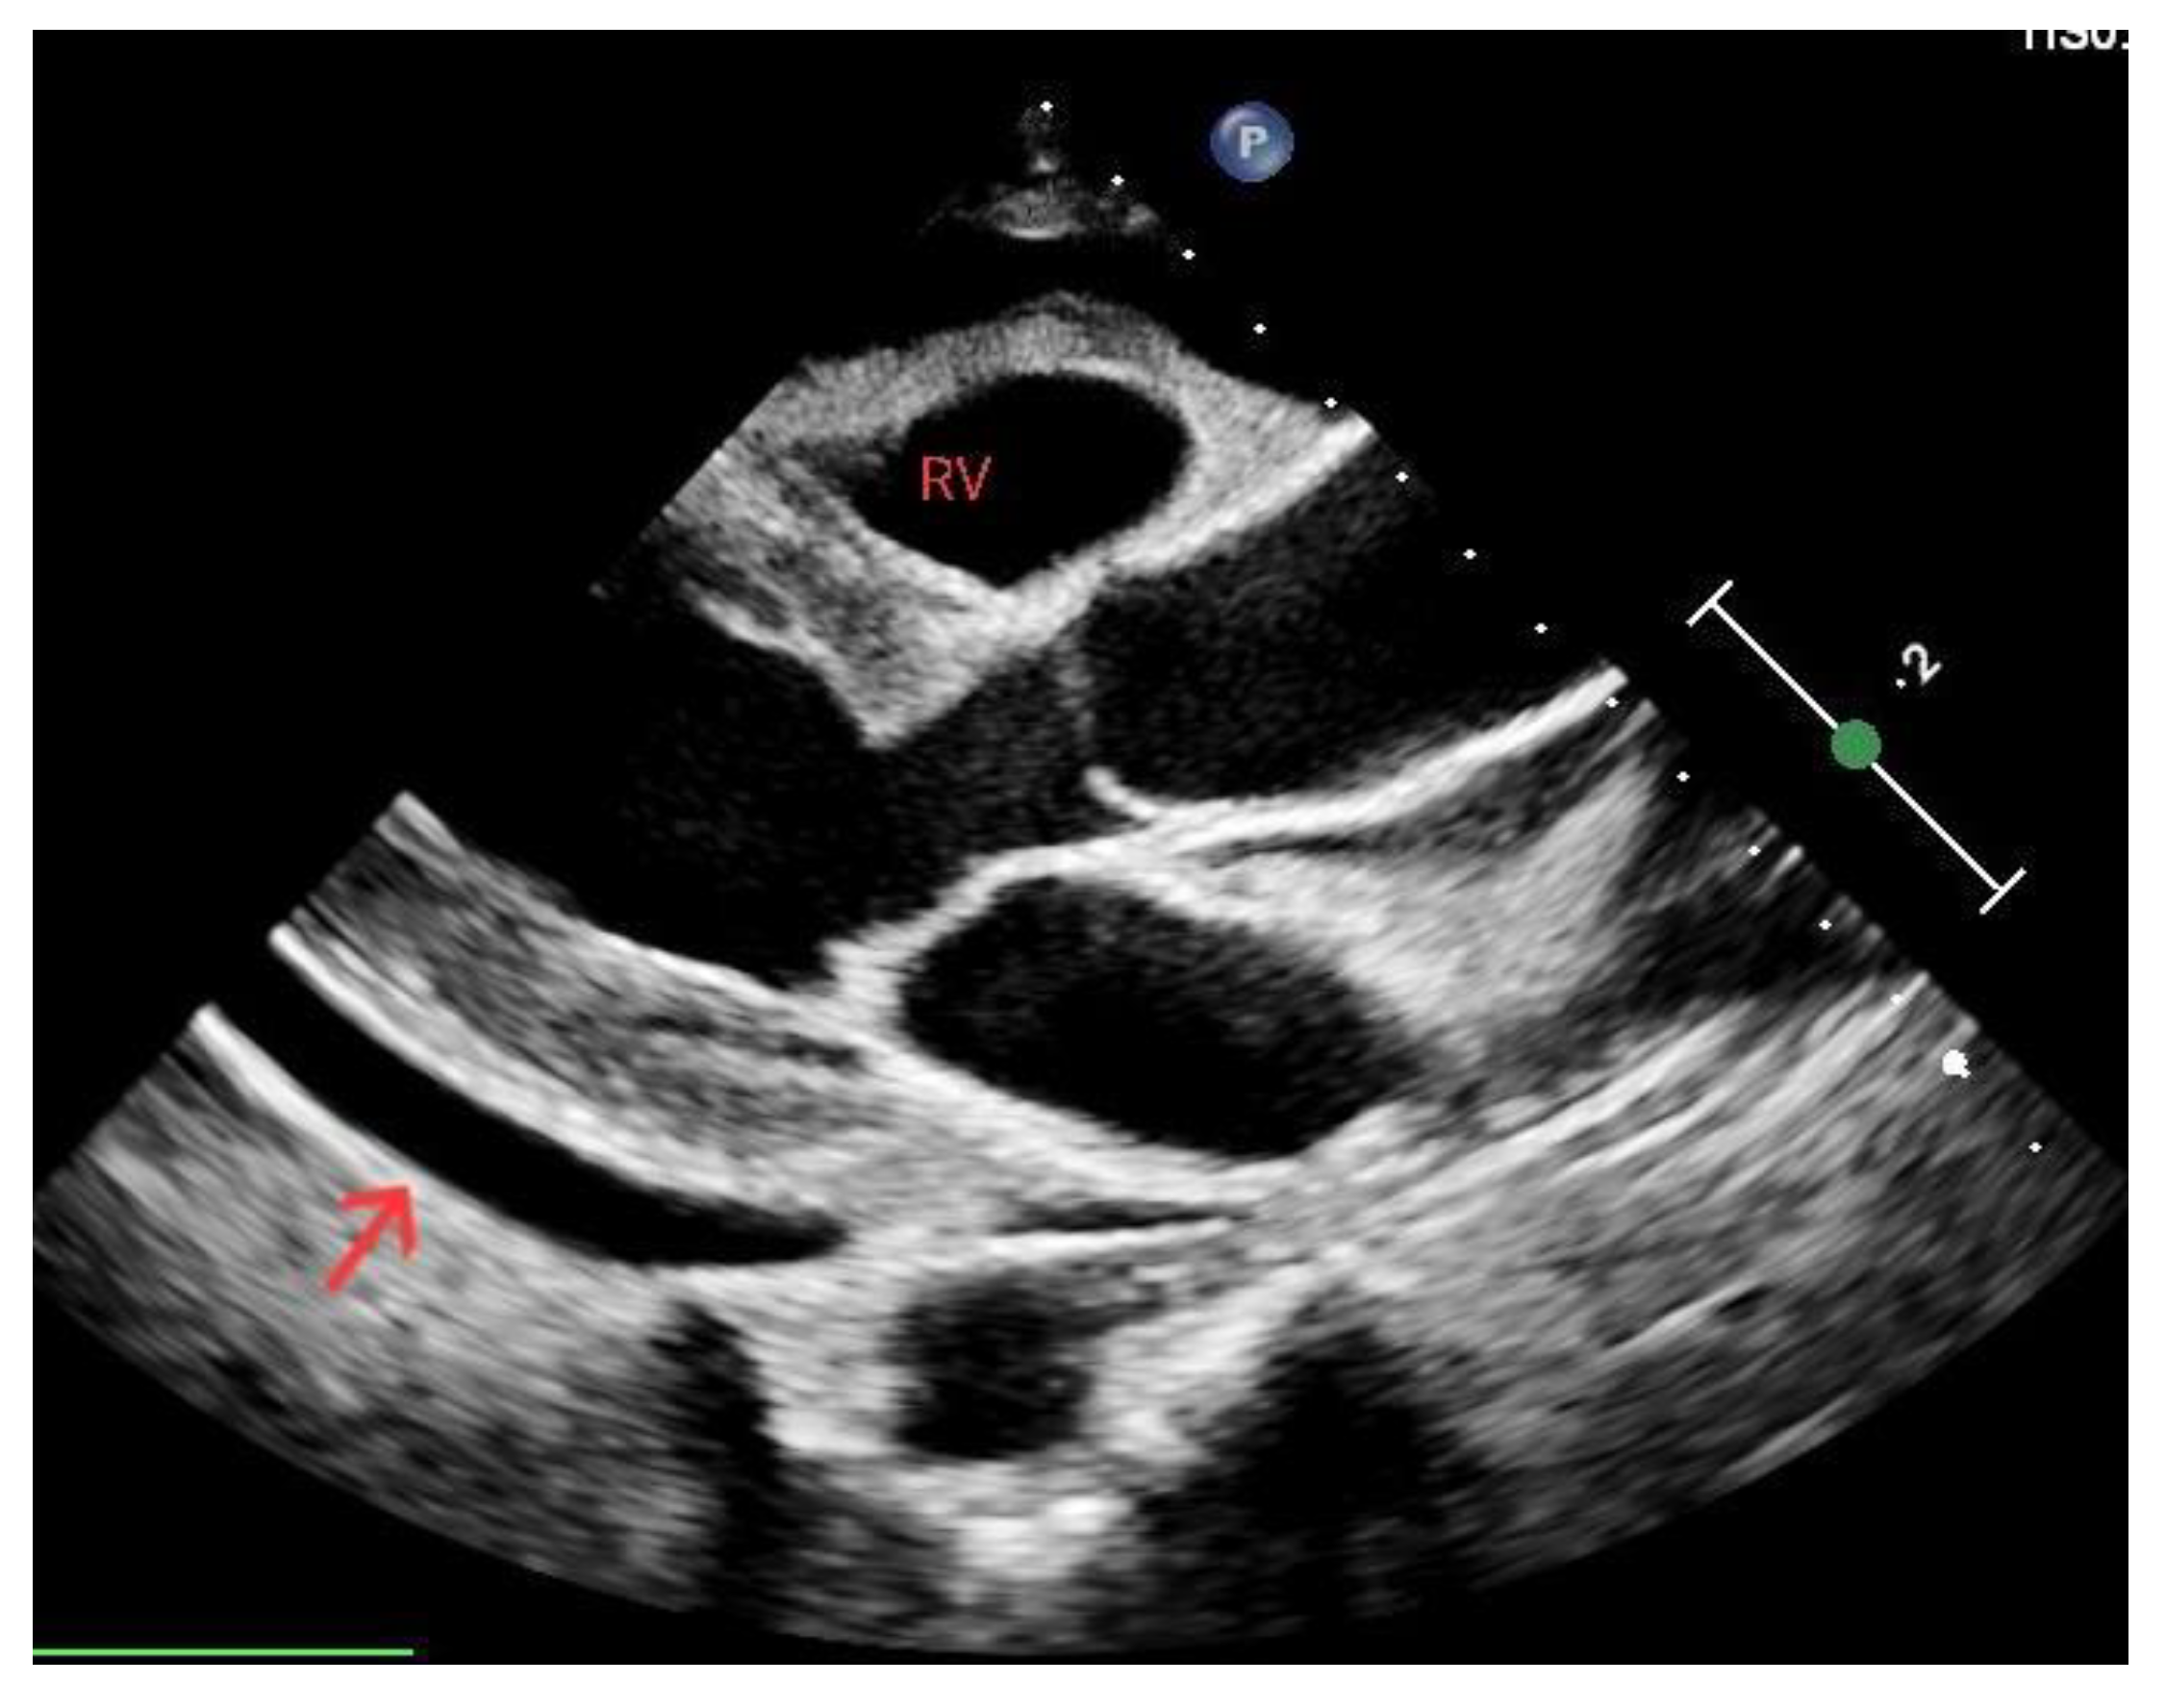

Cardiac arrest can result from hypovolemia due to decreased intravascular volume and extensive vasodilation. Hemorrhagic shock is the primary cause of death in this setting, especially in trauma patients [30]. While reduction in blood volume might be evident in traumatized patients, detecting the origins of internal bleeding presents a more considerable diagnostic hurdle, which can be addressed by employing ultrasound. The evaluation of size and function of the ventricles can aid in determining whether there is reduced cardiac filling due to decreased blood volume. Reduced left ventricular size might suggest hypovolemia [31]. The left ventricle might be hyperdynamic, with obliteration of the LV volume at the end of systole (Figure 5).

Figure 5.

Left ventricle (arrow) during diastole (a) and at the end of systole, obliterated and suggesting hypovolemia (b).

The inferior vena cava (IVC) acts as a vital blood reservoir, holding 85% of the total plasma volume within the venous circulation. Adjustments of circulating volume lead to variations in the caliber of the IVC. Indeed, the finding of a “flat vena cava” (e.g., an IVC with an anteroposterior diameter of less than 9 mm) at multiple levels is associated with significant hypovolemia (Figure 6) [32]. The IVC is usually visualized from a subcostal view via a longitudinal scan, including the veno–atrial junction and the right atrium with the inner walls clearly visible. In case of a suboptimal or unavailable subcostal window, a coronal transhepatic scan along the posterior right axillary line may be an effective alternative. Most authors suggest that measurements should be taken within 1.5 cm from the IVC-to-right atrial junction [33]. However, it is essential to consider that the interpretation of IVC measurements in the context of hypovolemia is not always straightforward. Venous congestion during CPR can limit the significance of the IVC assessment. Other factors such as intrathoracic pressure changes due to mechanical ventilation, individual patient characteristics, and concurrent medical conditions can influence IVC size and collapsibility [34,35].

Figure 6.

Normal (a) vs. collapsed IVC (b) indicated by the red lines, suggesting hypovolemia.